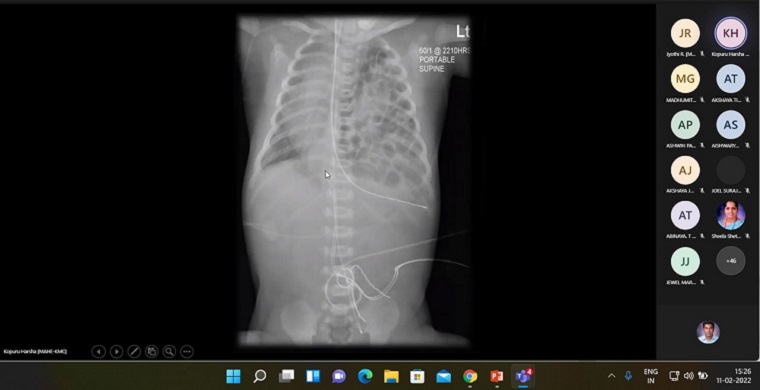

Guest Lecture on “Interpretation of Radiological Images”

Department of Medical-Surgical Nursing, Manipal College of Nursing, Manipal organized a Guest Lecture on “Interpretation of Radiological Images” on February 11, 2022, between 2.30 pm & 4.30 pm to students of BSc Nursing, Nurse Practitioner in Critical Care (NPCC) residential program and MSc Nursing through Microsoft Teams Platform. Dr Kopuru Harsha, Senior Resident, Dept. of Radiology, KMC Manipal spoke on the topic. He emphasized on reviewing the basic anatomy of the thorax, lungs and head and elaborated on the basics of radiological images of chest x-ray, CT thorax and CT head. A total of 65 participants including BSc, MSc and NPCC students and faculty members of MCON participated in the session.